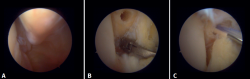

Arthroscopic evaluation of the syndesmosis

From the anteromedial portal we can directly visualize the distal fibers of the ATFL. Disinsertion of these fibers does not always result in instability of the syndesmosis, but it does require us to check it. In our experience, we prefer assessment of the coronal plane of the syndesmosis. We introduce the arthroscope into the tibiotalar joint directing the camera cranially. In this way we have a direct view of the distal tibiofibular joint. We then assess stability by attempting to insert the palpation probe into the joint. If it is possible to do so, we classify the syndesmosis injury as unstable (Figure 6A).

Arthroscopic evaluation of the deltoid ligament

There are multiple methods for assessing instability of the medial complex; using the anterior ankle portals it is possible to assess the stability of the deltoid ligament in its main plane of action, corresponding to the coronal plane. Chun et al.(20) described instability when it is possible to introduce an arthroscopic palpation probe into the medial tibiotalar space (Figure 6B). Vega et al.(21) reported that, in the majority of injuries, the most anterior portion of the deltoid ligament is detached from the medial malleolus, while its proximal insertions remain intact. In this situation, the arthroscopic palpation probe can be inserted between the medial wall of the internal malleolus and the deep fibers of the deltoid ligament.

Figure 6. Maneuvers to demonstrate ligament instability. A: lesion of the syndesmosis allowing insertion of the palpation probe into the distal tibiofibular zone; B: lesion of the deltoid ligament allowing insertion of the probe into the medial tibiotalar space.